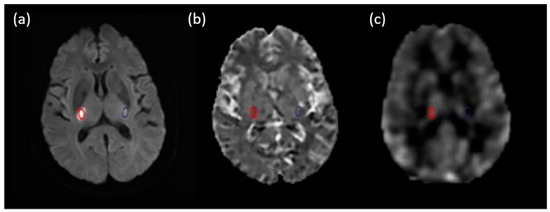

3.2. Image of Stroke Patients